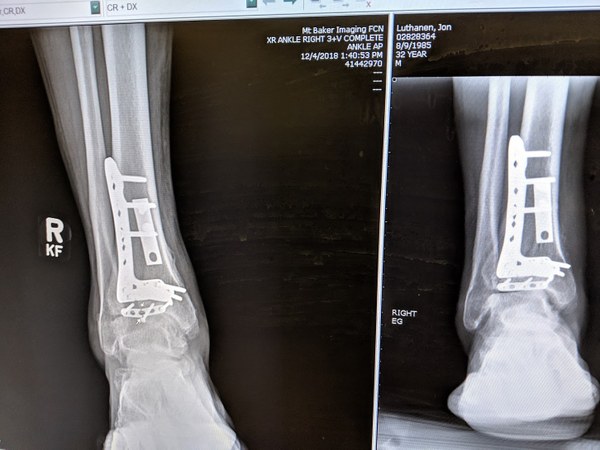

After additional X-rays and MRIs to both my foot and my wrist, which I had also landed on, I heard what every outdoorsy person never wants to hear. The urgent care doctor in Utah had said “Maybe surgery.” My orthopedic surgeon in Bellingham, Dr. Warren Taranow, said “No no – anyone who told you anything but surgery either has no idea what they’re talking about or didn’t want to ruin your summer. And I’m here to ruin your summer.” He told me I had sustained a severe pilon fracture to my right ankle, and the injury would permanently disable me.

I spent two months non-weight bearing on a one-legged scooter, one month in a walking boot with crutches, and an additional month with just the boot. It was three months of occupational therapy followed by three months of physical therapy for my wrist and ankle, respectively. Following physical therapy at the end of 2017, Cornerstone Orthotics & Prosthetics built me an AFO carbon fiber leg brace.

Plate break Dec 2018 (002).jpgHardware installed in Jon’s ankle. Photo courtesy of Jon Luthanen.

I'm actually back in a walking boot. In November I started testing my ability to run indoors, and I came away from a workout limping the next day – nauseous with every step. I thought I'd just overused my ankle, but went in for an X-ray. A bone spur had developed near the bottom of my tibia, and it collapsed and fractured one of the plates installed in my leg. The same surgical team went in and removed almost all of the hardware in February. I have another 6 weeks in a walking boot before I start physical therapy again.